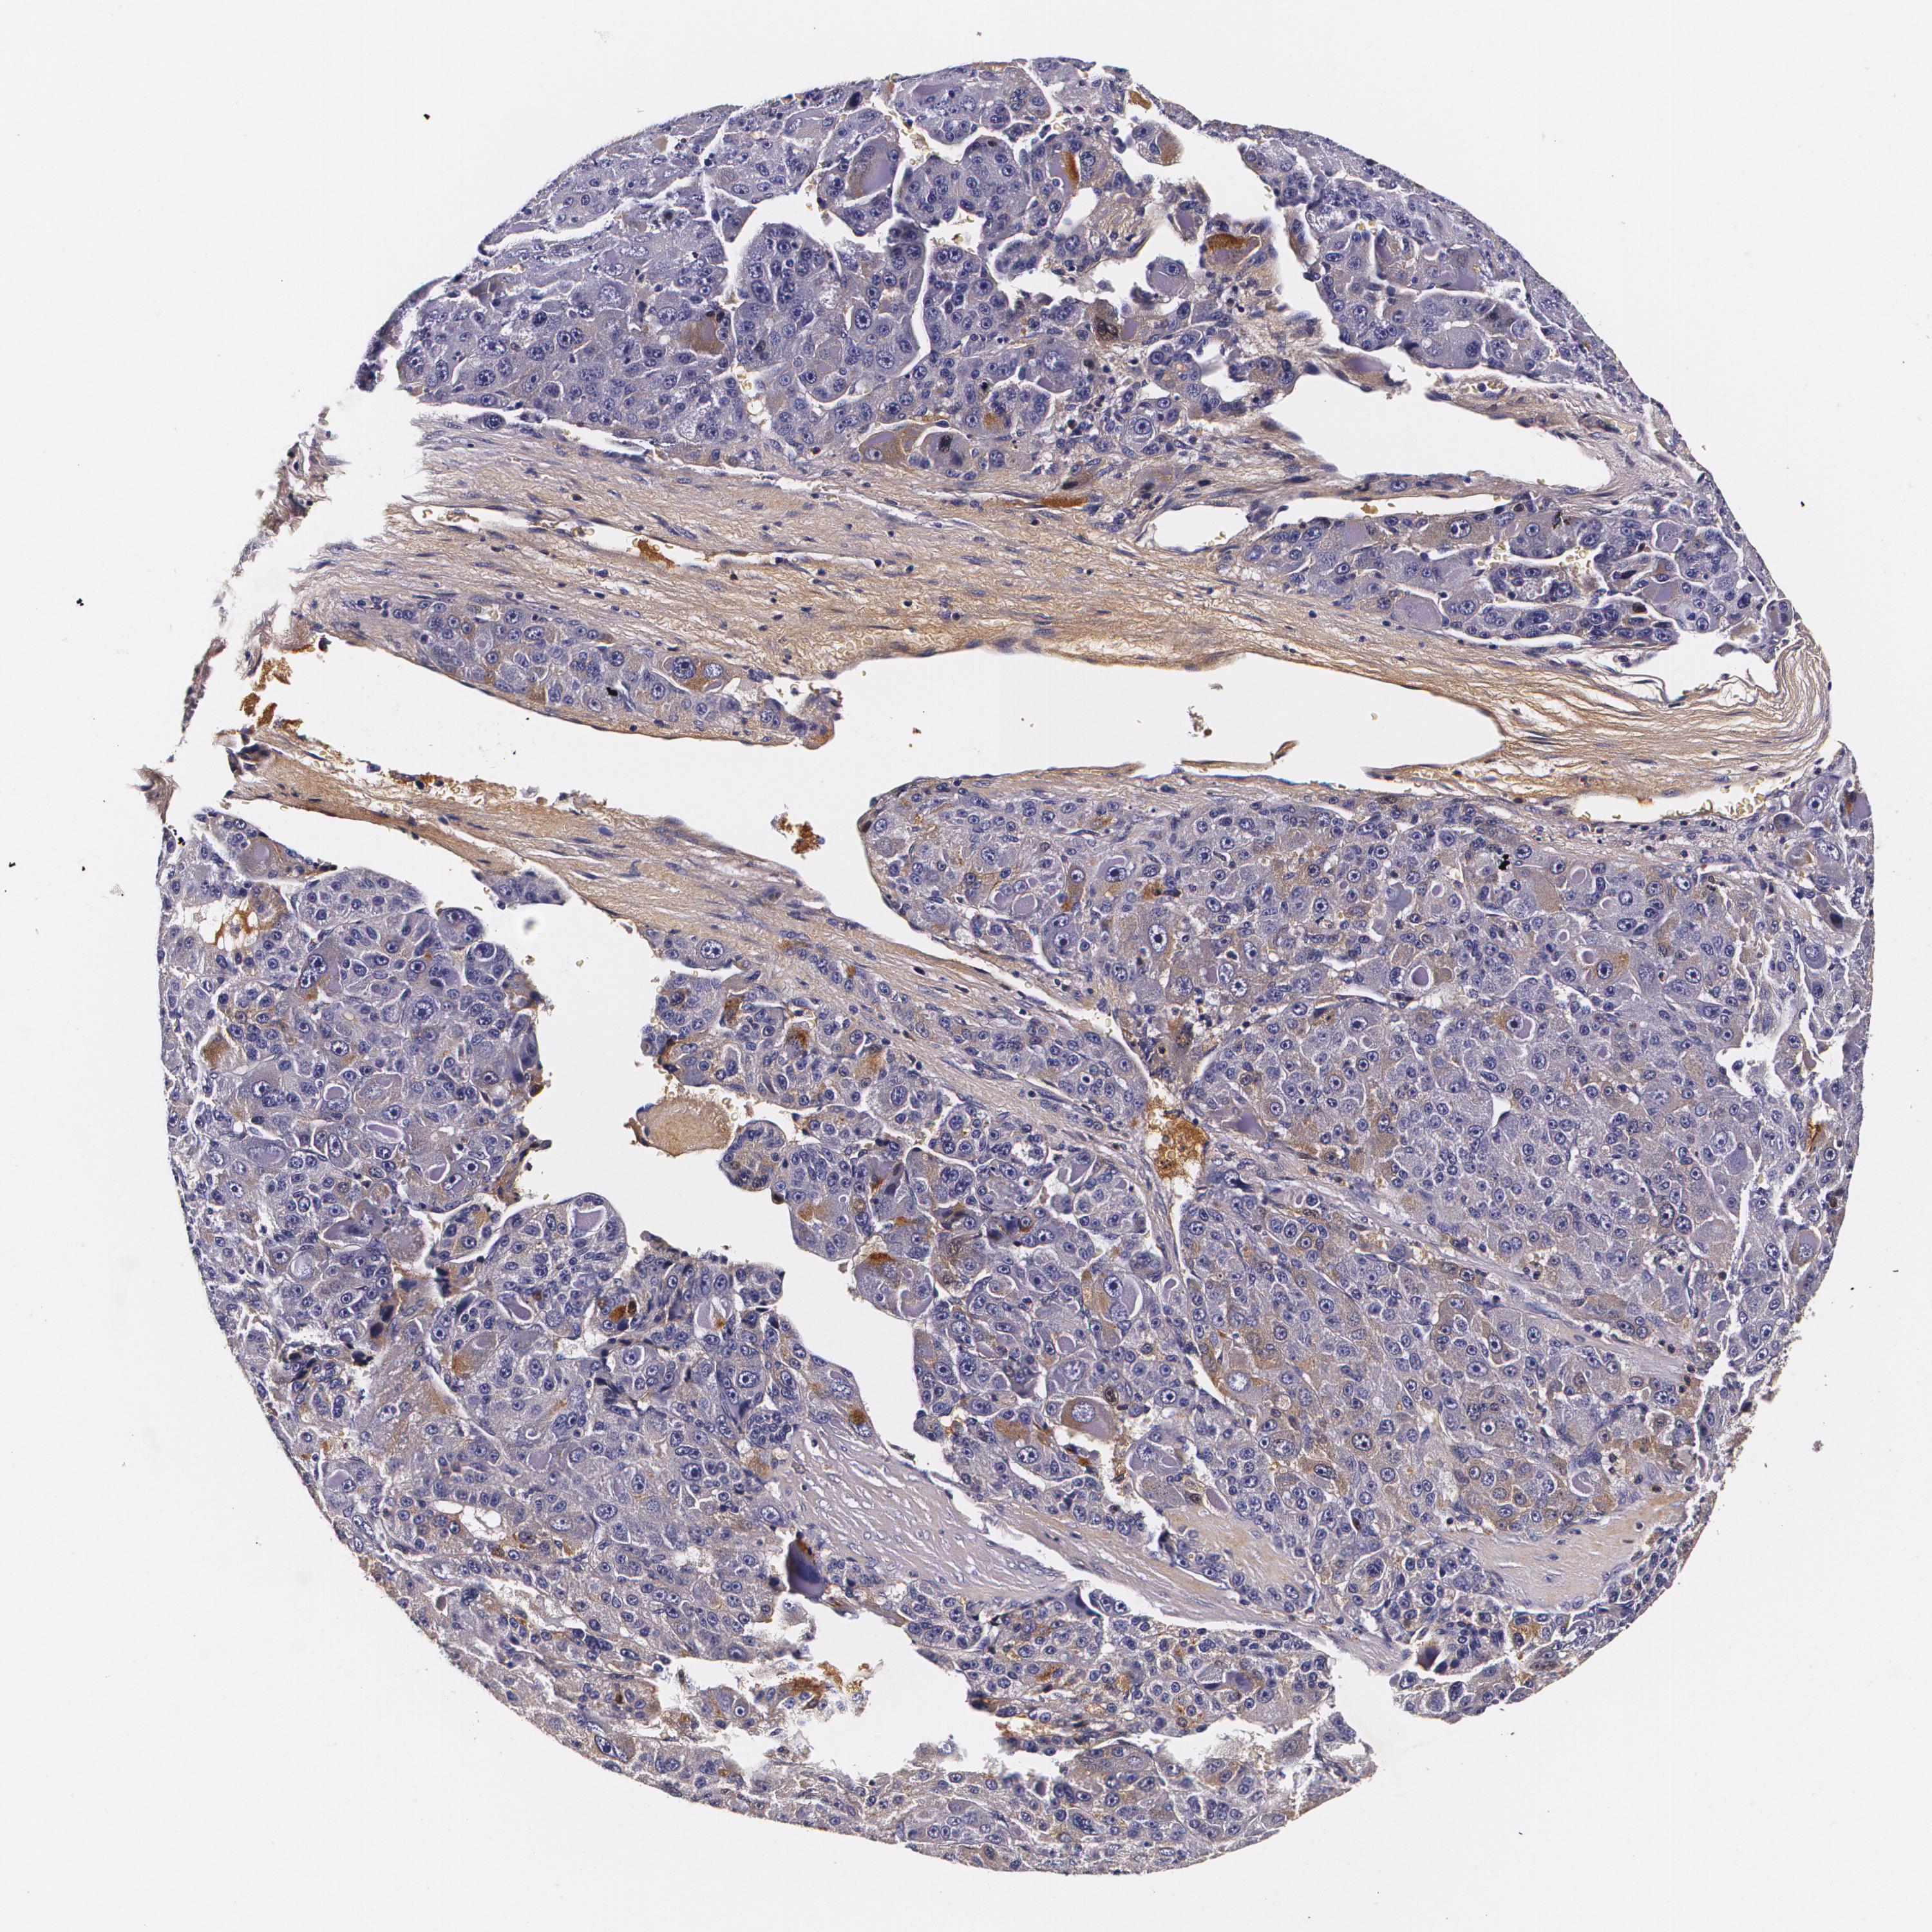

LIVER CANCER - Protein expressioni

A mouse-over function shows sample information and annotation data. Click on an image to view it in a full screen mode. Samples can be filtered based on level of antibody staining by selecting one or several of the following categories: high, medium, low and not detected. The assay and annotation is described here.

Note that samples used for immunohistochemistry by the Human Protein Atlas do not correspond to samples in the TCGA dataset.

Antibody stainingi

Antibody staining in the annotated cell types in the current human tissue is reported as not detected, low, medium, or high, based on conventional immunohistochemistry profiling in selected tissues. This score is based on the combination of the staining intensity and fraction of stained cells.

Each image is clickable and will lead to virtual microscopy that enables deeper exploration of all samples and also displays staining intensity scores, fraction scores and subcellular localization as well as patient and tissue information for each sample.

Antibody HPA002550

Antibody CAB002517

Antibody CAB062567

Antibody CAB073406

Staining

High

Medium

Low

Not detected

Intensity

Strong

Moderate

Weak

Negative

Quantity

>75%

75%-25%

<25%

None

Location

Nuclear

Cytoplasmic/membranous

Cytoplasmic/membranous,nuclear

Carcinoma, Hepatocellular, NOS

Cholangiocarcinoma